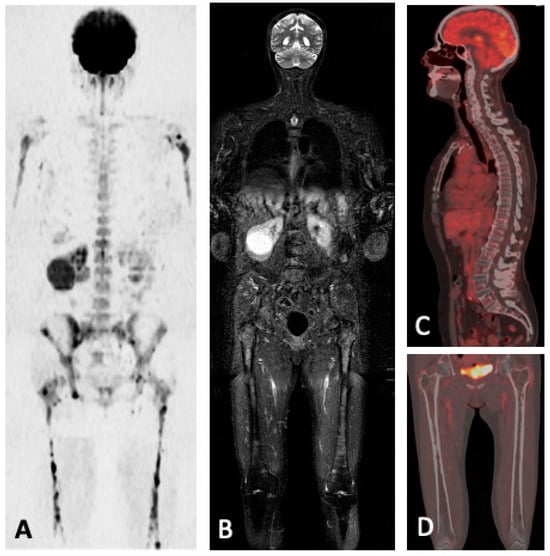

5.2. FDG-PET/MRI